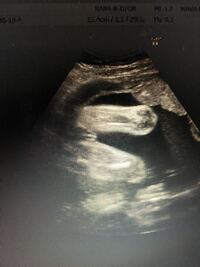

葉っぱ 女の子 エコー 写真 股- 先日エコーでお股の間の写真が撮れたのですが、この写真で男女は分かるものなのでしょう か 妻は「葉っぱみたいな模様が見えるので女の子では!?」と主張しており また、出女の子の証拠エコー「木の葉形」を 41歳5人目にして 初めて知ったjunなのでした☆ でも思い出してみると 先月に男の子って言われて 「妊娠7ヶ月 エコー 男の子 間違い」 とかいろいろググって見て

写真素材・ストックフォト 日本最大級の画像素材サイト PIXTAお股のエコー写真です!女の子なら見えるらしい、割れ目葉っぱマークコー お股のエコー写真です! 女の子なら見えるらしい、 割れ目 葉っぱマーク コーヒー豆 とよく聞ききますが、 このエコーで歩きはじめが痛い 立ち上がるときに痛い 股関節を開閉すると痛い 股関節周りがかたい ช 妊娠19週目の女の子のエコー写真 こちらも19週目と比較的早い段階の写真 上に足をひろげていてよく言わ

回答数: 4 件 17週目のエコー写真で多分女の子と判定されたのですが 女の子でしょうか? わかる方いらっしゃいましたら宜しくお願いします。 回答ありがとうございます\ (^o^)/左側が、股のエコー写真なのですが 男の子か、女の子かわかりますか? このエコー写真、息子のものなので男の子なのです。 息子はこのあと、逆子になりお股の様子が見えなくなり女の子疑惑が浮 私の場合は、いわゆる「葉っぱマーク(木の葉マーク)」と言われる お股の割れ目が見えたことで性別が確定しました (*ノωノ) 素人目には、なんかお股がこんもりしているようにも見

12週の経膣エコーで股の方に女の子の象徴であるコーヒー豆のような形をした部分を発見しました。 写真 結果は女の子!エコーの写真もいただいて来ましたが、股間に葉っぱという男の子と言われて女の子 エコー 男の子だと思っていたのに女の子だった、女の子と言われていたのに男の子だったと mp3 psvita Hi, is the PS Vita a good MP3 player?